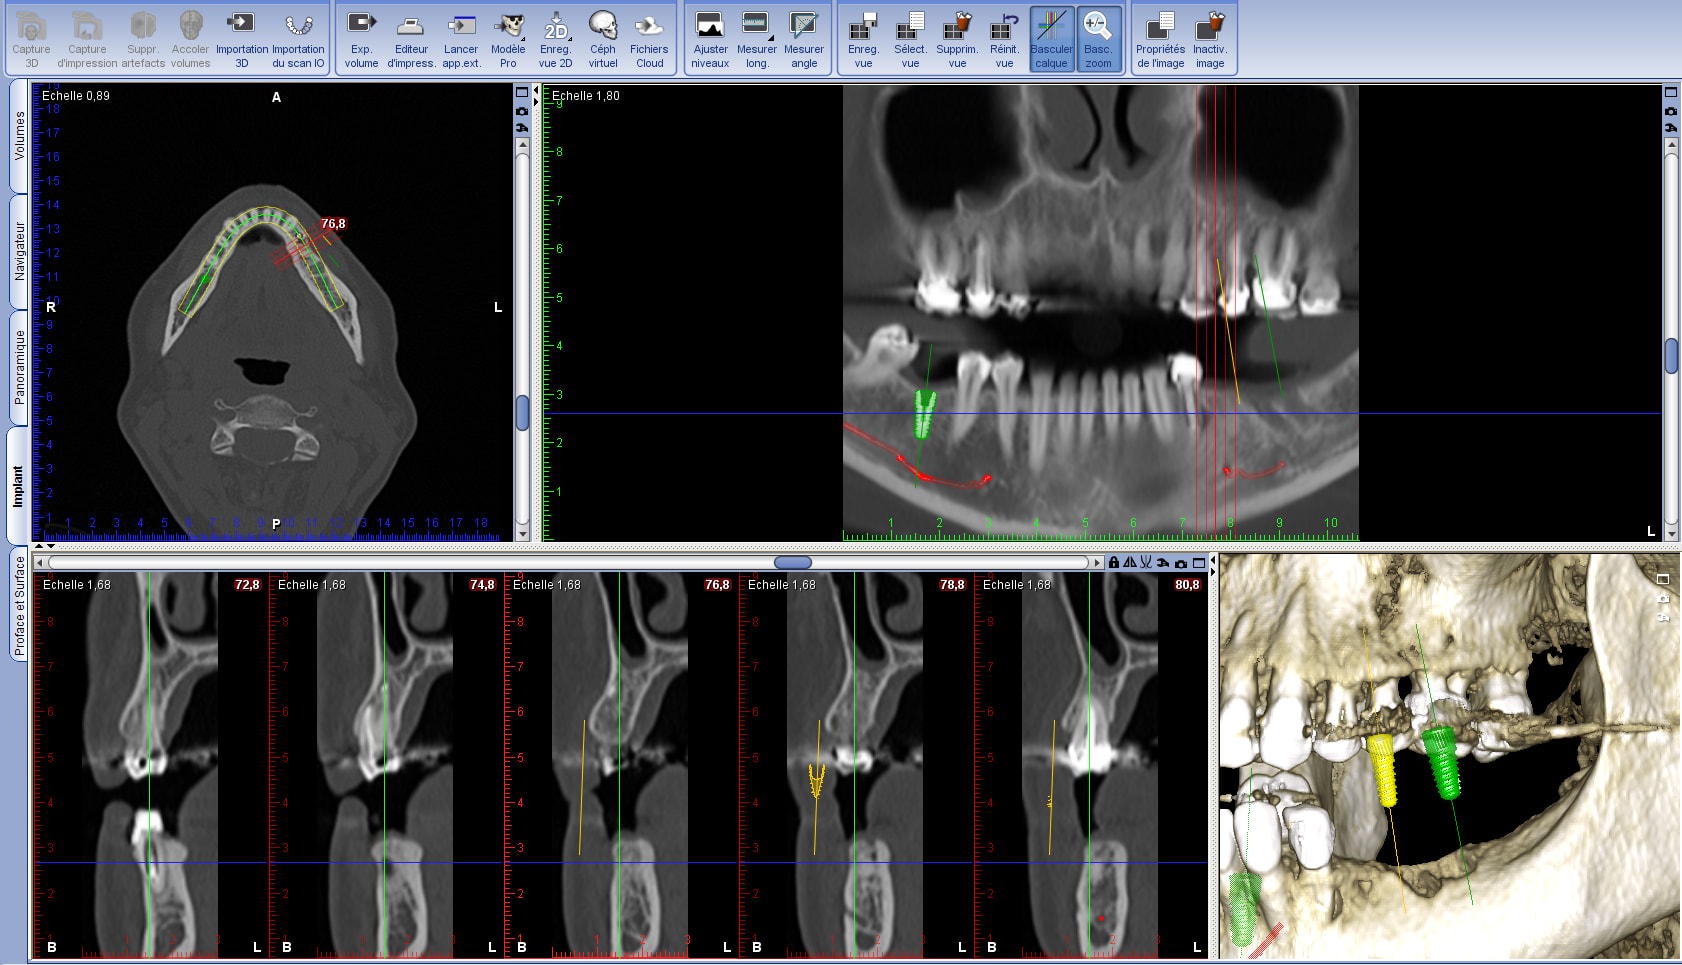

Merci ! et voila outil de capture fait. J'ai mis la page entière pour situer les coupes... La qualité du scan n'est tjs pas top ( c'est intrinsèque à la qualité du scan) mais j'espère que cela ira.

Sur la reconstruction 3D, j'ai l'impression qu'un bout de racine dépasse en vestibulaire.. Sur 36 pensez vous qu'une ROG sera nécessaire... Si oui, si je comble avec des copeau osseux sans membrane vu que ça semble mineur, cela se calicifiera ?

la 34 est à mettre à la poubelle....c'est fissuré => image latérale

Merci pour ton com’ . Oui c’est certain, 34 est HS. Mais 3 problemes semblent se poser.

1) comment enlever l’apex fracture de 34 sans delabrer

2) sur la reconstruction 3D, j'ai l'impression qu'un bout de racine dépasse en vestibulaire..

3) Sur 36 pensez vous qu'une ROG sera nécessaire... Si oui, si je comble avec des copeaux osseux sans membrane vu que ça semble mineur, cela se calcifiera ?